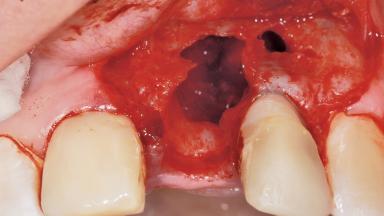

Late Placement of an Implant in a Maxillary Left Central Incisor Site

A 36-year-old female patient was referred for the replacement of the upper left central incisor (tooth 21), which had fractured. Although the tooth had been asymptomatic for many years, the crown began to loosen, at which time she presented to her dentist for an assessment. Teeth 21 and 22 had both been endodontically treated many years previously. She was a healthy individual and a non-smoker.

The crown of tooth 21 was splinted to the adjacent teeth with composite resin, and the gingiva was inflamed.